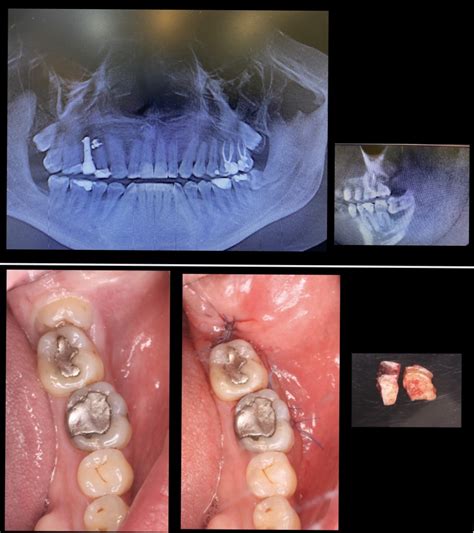

Procedimiento de Extracción de Muelas del Juicio

La técnica quirúrgica consiste en anestesiar, con anestésico local, la zona periférica de la pieza a extraer. Antes de planificar la cirugía, es fundamental realizar un estudio bucodental completo al paciente, el cual está basado en una serie de pruebas clínicas y radiográficas. Lo más habitual es administrar anestesia local. Sin embargo, cuando es necesario extraer más de dos muelas del juicio en la misma cirugía se puede administrar sedación o anestesia general. La intervención se lleva a cabo, por norma general, con anestesia local más sedación. En el caso de tratarse de una extracción múltiple (las 4 muelas del juicio a la vez) se podría efectuar con anestesia general.

- Extracción quirúrgica: Dentro de la extracción quirúrgica debemos distinguir dos situaciones: la muela que ha erupcionado de manera parcial y la que se encuentra totalmente incluida en la encía. En ambos casos, el cirujano deberá realizar una incisión en la encía para exponer el diente y el hueso. Si hay hueso cubriendo el diente, este será apartado cuidadosamente para llegar al diente.

Una vez extraído el diente, se limpia la zona cuidadosamente para eliminar cualquier fragmento o residuo que haya quedado. El cierre de la herida se llevará a cabo con puntos de sutura reabsorbibles o con sutura quirúrgica (esta se retira entre 5 y 8 días después de la intervención). Tras la extracción, se coloca una gasa en la zona intervenida para controlar el sangrado y contribuir a la formación del coágulo.